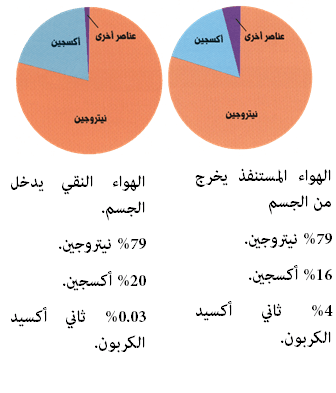

الهواء و معدلات التنفس

هناك معدلات متوسطة من حجم الهواء الداخل الرئتين بالنسبة للرجل البالغ، أما بالنسبة للنساء، فتقل هذه الكميات بمقدار الربع.

تبادل منصف

•إن التنفس لا يعني فقط إدخال الأكسجين، وإنما يعني أيضاً التخلص من الفضلات الناتجة عن عملية التنفس، وهي ثاني أكسيد الكربون، والذي يؤدي تراكمه إلى تسمم الجسم.